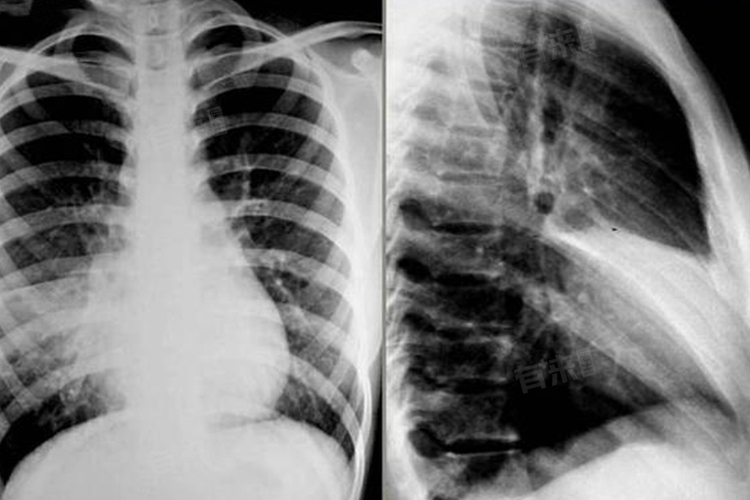

肺不张的症状多样且严重程度不一,其症状的出现和严重程度与肺不张的范围、病因以及患者的基础健康状况密切相关。一旦出现上述症状,应及时就医,进行详细的检查,如胸部X光、CT扫描等,以明确诊断并采取相应的治疗措施。